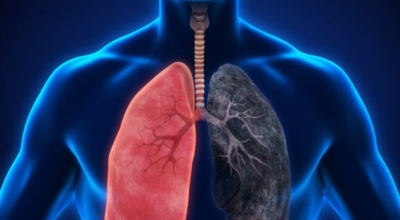

폐암의 공통 위험요소로 손꼽히는 이유가 되는 것으로 흡연이 있습니다. 흡연자는 비흡연자에 비교해 십몇 배는 더 폐암 발병확률이 높다고 하며 어느정도 기간 동안 흡연했는지에 따라 폐암 발생확률은 더더욱 더 높아집니다. 흡연자라고 해도 금연을 하게 되면 폐암 발병확률이 빠르게 내려간다고 하니 폐암이 걱정되신다면 가장 먼저 금연은 필수입니다.